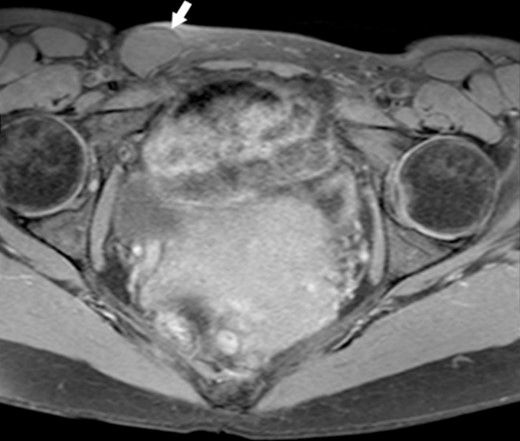

A 44-year-old Caucasian woman presented in our clinic with a painless swelling in the right inguinal region that appeared 10 months before her hospitalisation. A small soft mass measuring 4 × 2 cm2 was found on the physical examination. There were no changes in size or shape in the lesion when performing the Valsalva manoeuvre. Magnetic resonance imaging (MRI) showed an oval cyst measured 3.9/2.6/2.4 cm close to the uterus’s round ligament in the right inguinal channel. The lesion was hypointense in T1- (Fig. 1) and hyperintense in T2-sequence (Fig. 2). An anechoic cyst was observed using ultrasound. The cyst was classified as type I based on Counseller and Black’s classification [2]. Blood analysis showed no pathological changes.

MRI of the Cyst of the Canal of Nuck–T1 sequence. This image highlights the cyst (indicated by the white arrow) within the inguinal region.